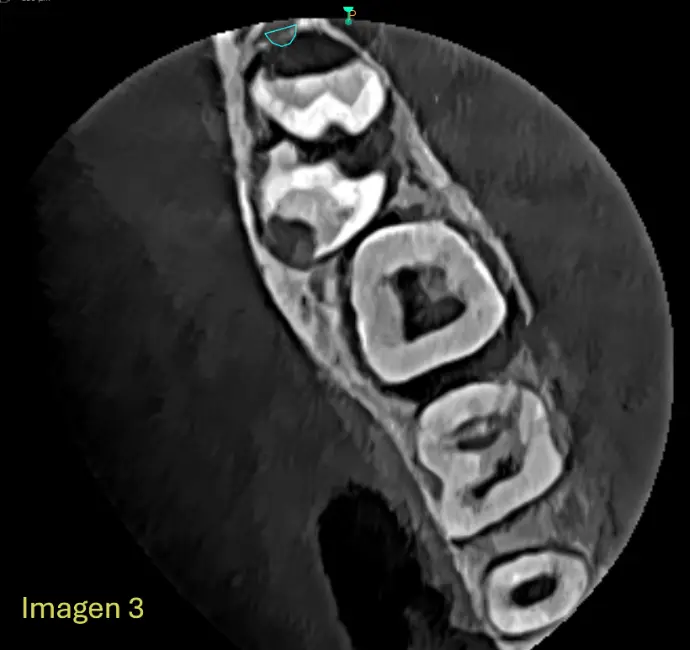

​Se Observa en la Cone Beam la formación dentro de un mismo saco coronario la formación de dos estructuras coronarias, correspondiendo a Pd 48 y Pd 49 (4to molar) Ambas piezas en proceso de formcion, completamente incluida, en intimo contacto con el conducto dentario inferior derecho sin signos de desplazamientos evidentes (IMG. 2), Ambas piezas dentarias se encuentran incluidas con la corona enfrentadas (IMG. 3),